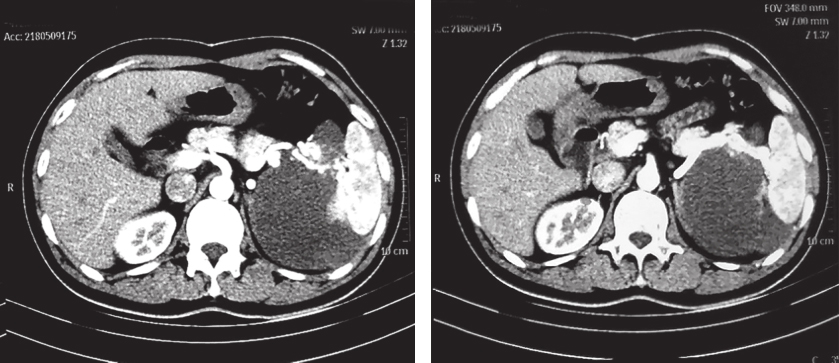

患者服药18个月后复查CT示:与前片比较,软组织密度影范围无显著变化。患者考虑个人时间安排原因,决定延后手术时间(图2)。

图2 2018年5月9日增强CT